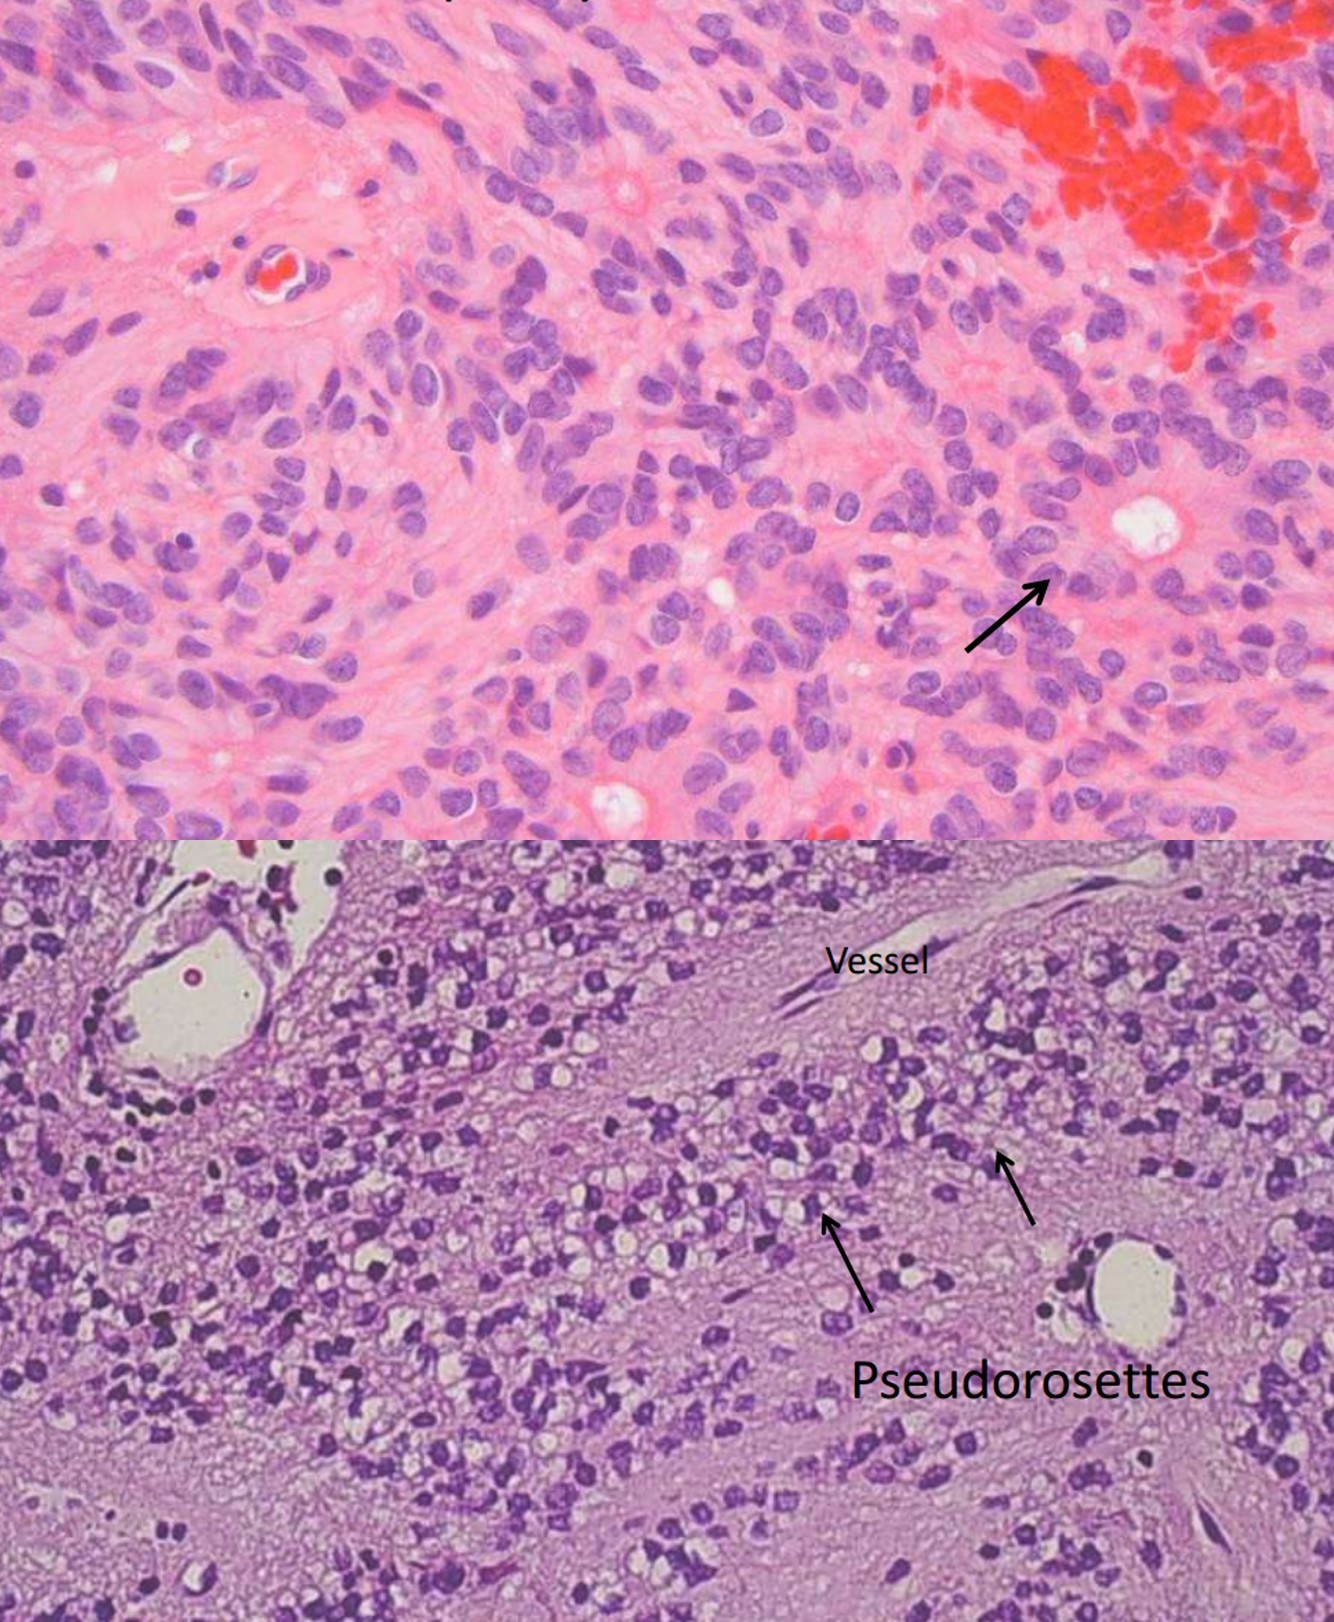

Ependymoma

- Incidence: 5% to 10% of primary brain tumors in the 1st two decades

- Arise around ventricular lining

- Locations:

- The 4th ventrical: common in children

- Spinal: adults, mean 40 yrs, NF2

- Loss/mutation of NF2 on chromosome 22q in spinal cord tumors